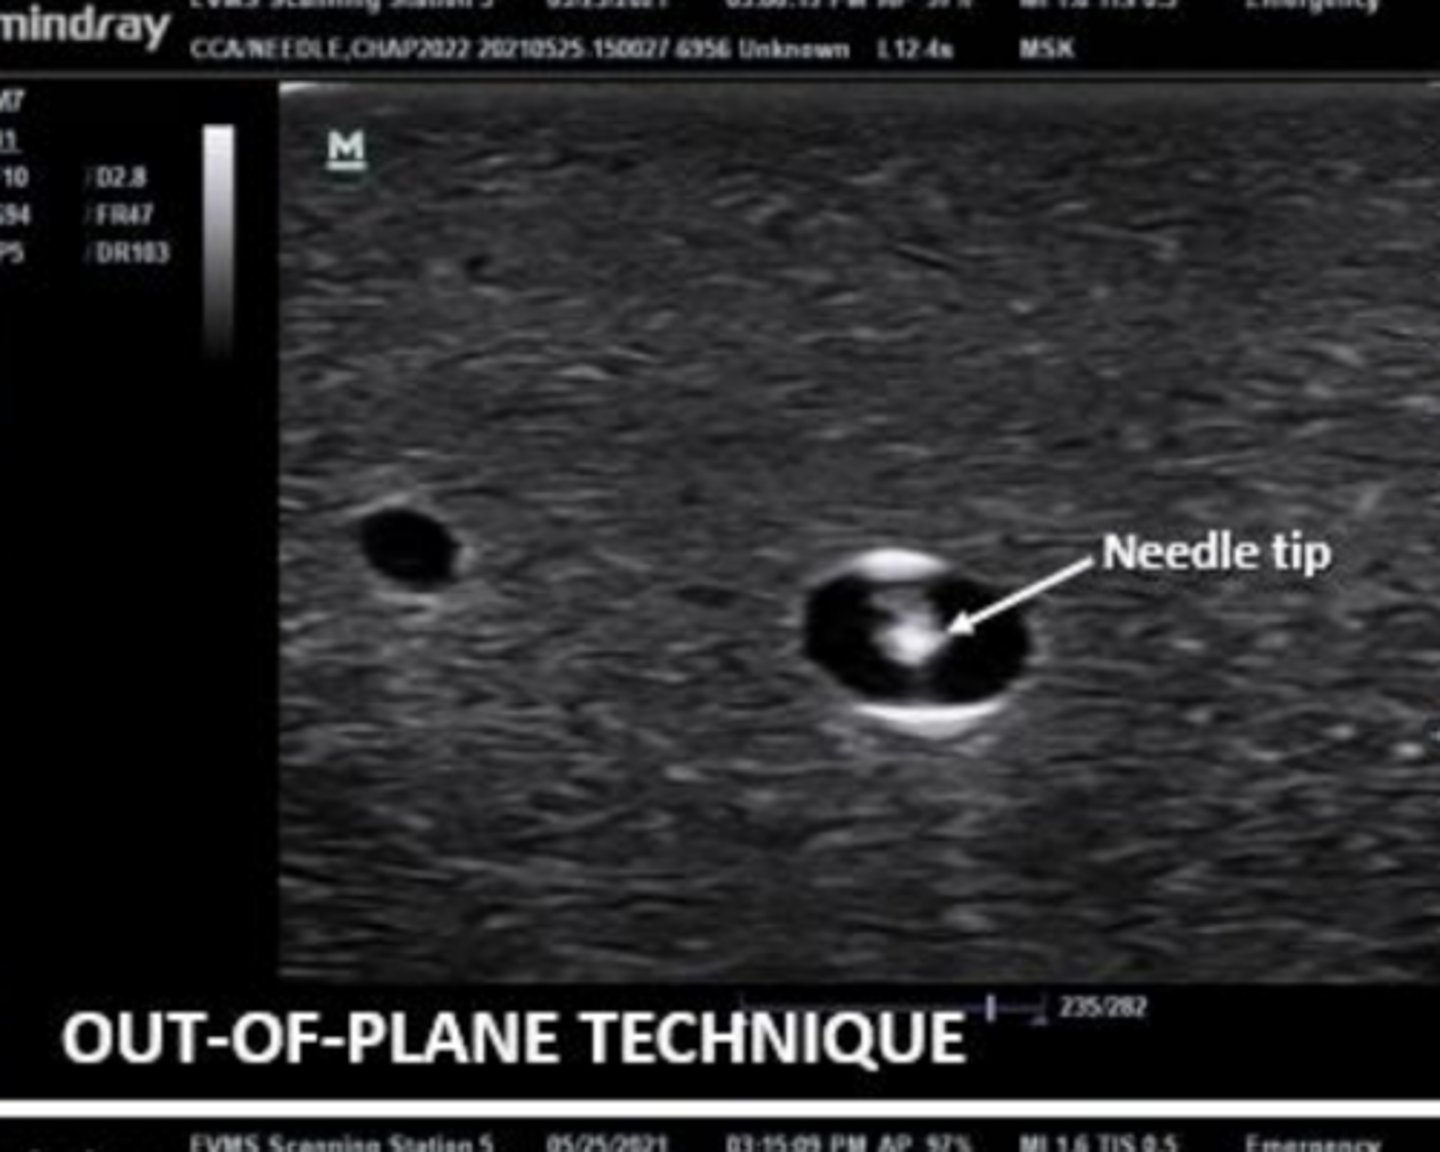

is this an out of plane or in plane view